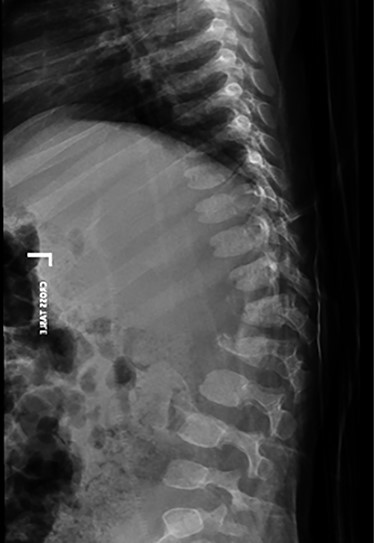

(A) sagittal thoracolumbar CT scan. (B–D) Axial thoracolumbar CT scan. (A-D) There are compression fractures and decreased vertebral body height of T12 and L1 with left pedicle and spinous process fractures. These fractures are associated with bony fragments within the spinal canal causing narrowing of the spinal canal at the same level. There is a nondisplaced fracture at the spinous process of L3 and the left transverse process of T10.

A spine radiograph and CT scan (Figs 1 and 2) revealed a three-column fracture of T12-L1 and an L2 body fracture. A multiplanar and multisequential MR images (Fig. 3) of the whole spine were performed utilizing trauma protocol. The images demonstrated narrowing of the spinal canal at the level of thoracolumbar junction secondary to multilevel fractures along with myelomalacia changes involving the lower thoracic cord and conus medullaris. Additionally, the images showed an evidence of kyphosis measuring 47° at the fracture site.